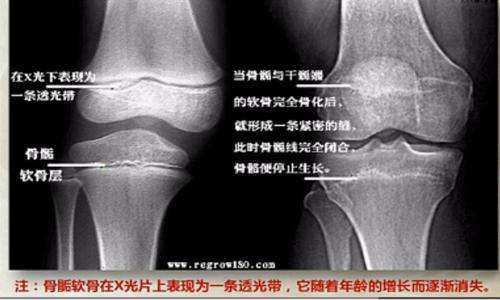

在骨骺线闭合之前,骺软骨不断分裂增殖生成新的软骨,然后软骨变成骨

随着年龄的不断增长,骨骺线逐渐的钙化,当它完全钙化之后,人体就没有

其实,人体骨骺线完全彻底的钙化闭合是一个极为缓慢的过程,大概(18-33

在这段时间里人体骨骺线基本闭合,同时骨骼逐渐钙化,人体也逐渐停止